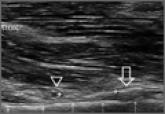

Clinical and Sonographic Evaluation of Bicortical Button for Proximal Biceps Tenodesis

Use of a cortical button for proximal biceps tenodesis has demonstrated strength comparable to that of other types of fixation in biomechanical...